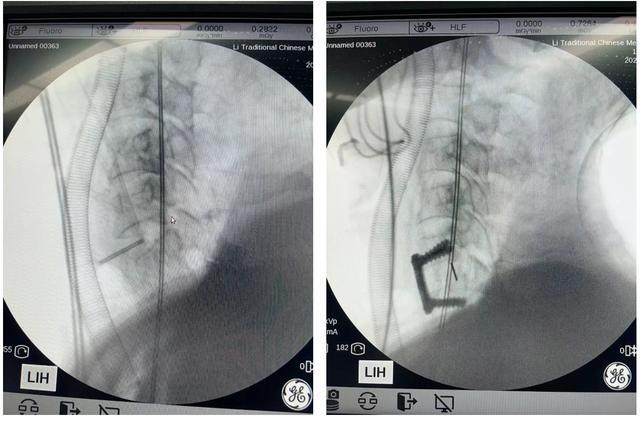

手术历时1.5小时,出血量不足50ml,术后影像显示,患者椎体脱位完全纠正、减压充分、内固定位置精准稳定。术后第三日,患者即可佩戴支具下地活动,基本生活能够自理,疼痛显著减轻,吞咽功能未受影响,手术疤痕隐蔽美观,目前正接受规范化康复训练。